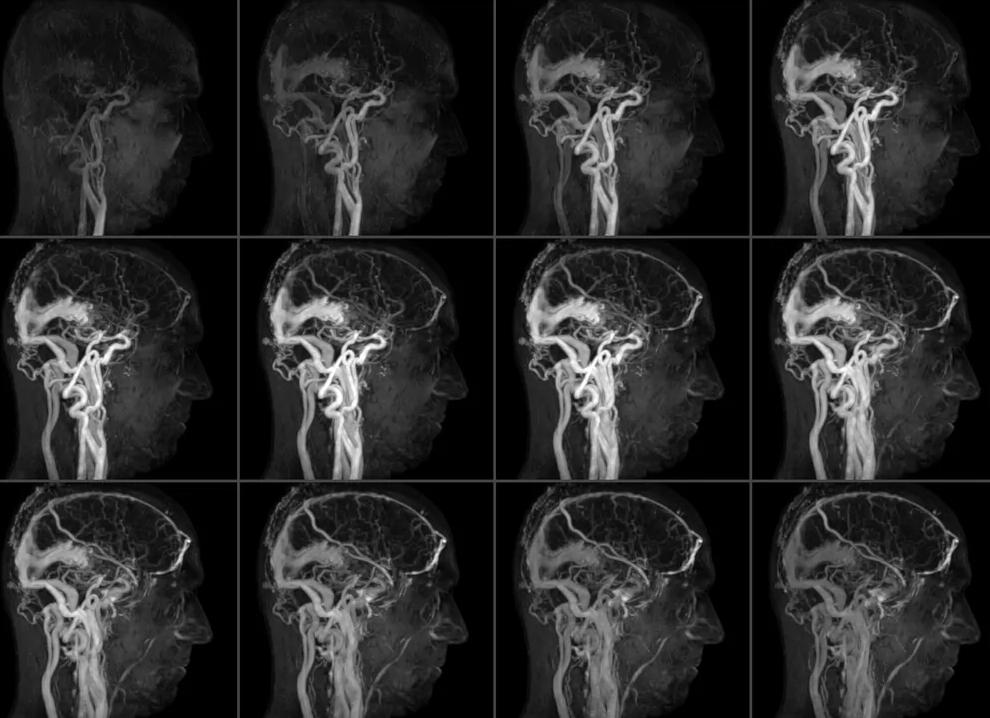

Пример магниторезонансной ангиограммы

Таким образом, благодаря разным видам МР ангиографии (фазово-контрастной, времяпролетной, 4Д) получают двухмерные или трехмерные изображения не самих сосудов, а циркулирующей по ним крови.

В процессе исследования специалист получает абсолютно достоверное и детализированное изображение сосудов: нормальные артерии и вены имеют ровный и четкий контур, без петель и резких загибов, утолщений по ходу уменьшения просвета (сосудистые «ветки»).

Этот метод ангиографии дает возможность визуализации тонких срезов сосудистой сети, создания ее трехмерной схемы.

На полученных проекциях специалист видит изображения сосудов всех зон головного мозга. Он получает возможность кровоснабжение как всего головного мозга и его оболочек, так и отдельных его структура, увидеть патологические изменения.